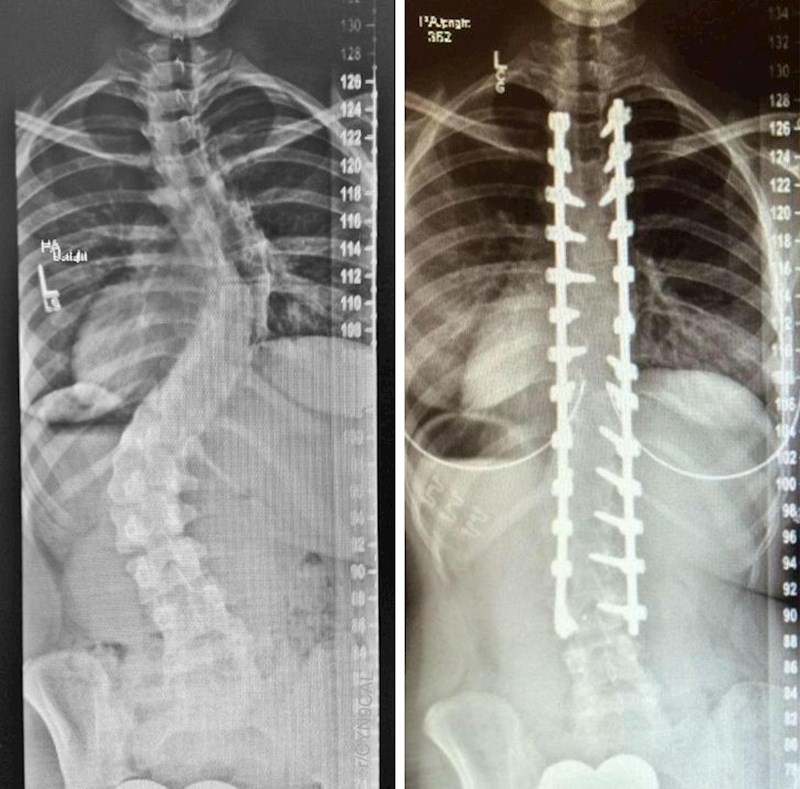

7. Moja kralješnica prije i poslije operacije.